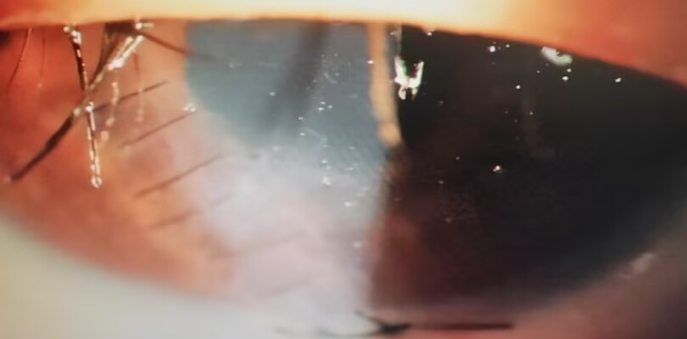

这是一场在显微镜下的“针尖芭蕾”。

没有现成的模板可抄,没有成熟的经验可依。但曾健医生凭借深厚的功底,在方寸之间的眼球上,开始了一场惊心动魄的修复。

清创、取出异物、精细还纳脱出的虹膜、缝合破裂的眼球壁……每一秒,都在和黑暗赛跑。

结果,是完美的!

不仅成功保住了眼球,避免了摘眼的悲剧,更最大程度地挽救了孩子的视力!